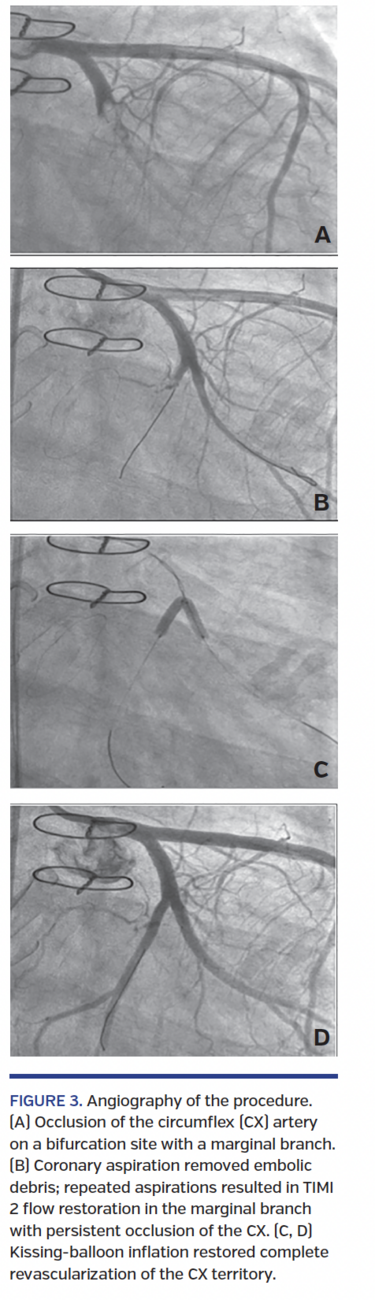

Given the episodic fever, we rapidly performed an echocardiography before cardiac catheterization that showed a 2 cm irregular mobile formation attached to the bioprosthetic mitral valve (Figure 2) and an impaired left ventricular ejection fraction of 35% with akinesis of the inferior and inferolateral walls.